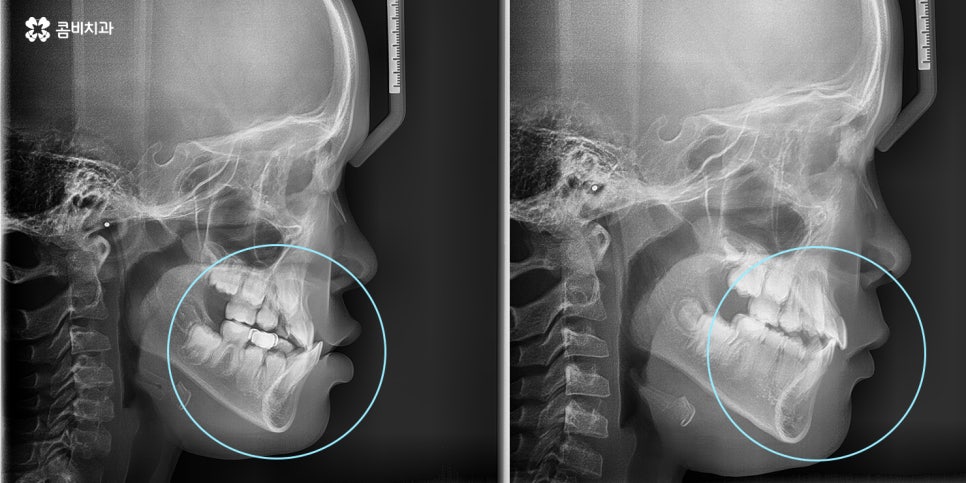

(3개월 정도 후 성장 조절 치료를 통해서 주걱턱이 점점 개선되고 있는 모습)

(반대교합, 주걱턱 교정치료가 시작된지 1년 후의 모습)

앞니가 반대로 물리고 있던 상황(주걱턱)에서 정상적으로 앞니가 물리게 되었음